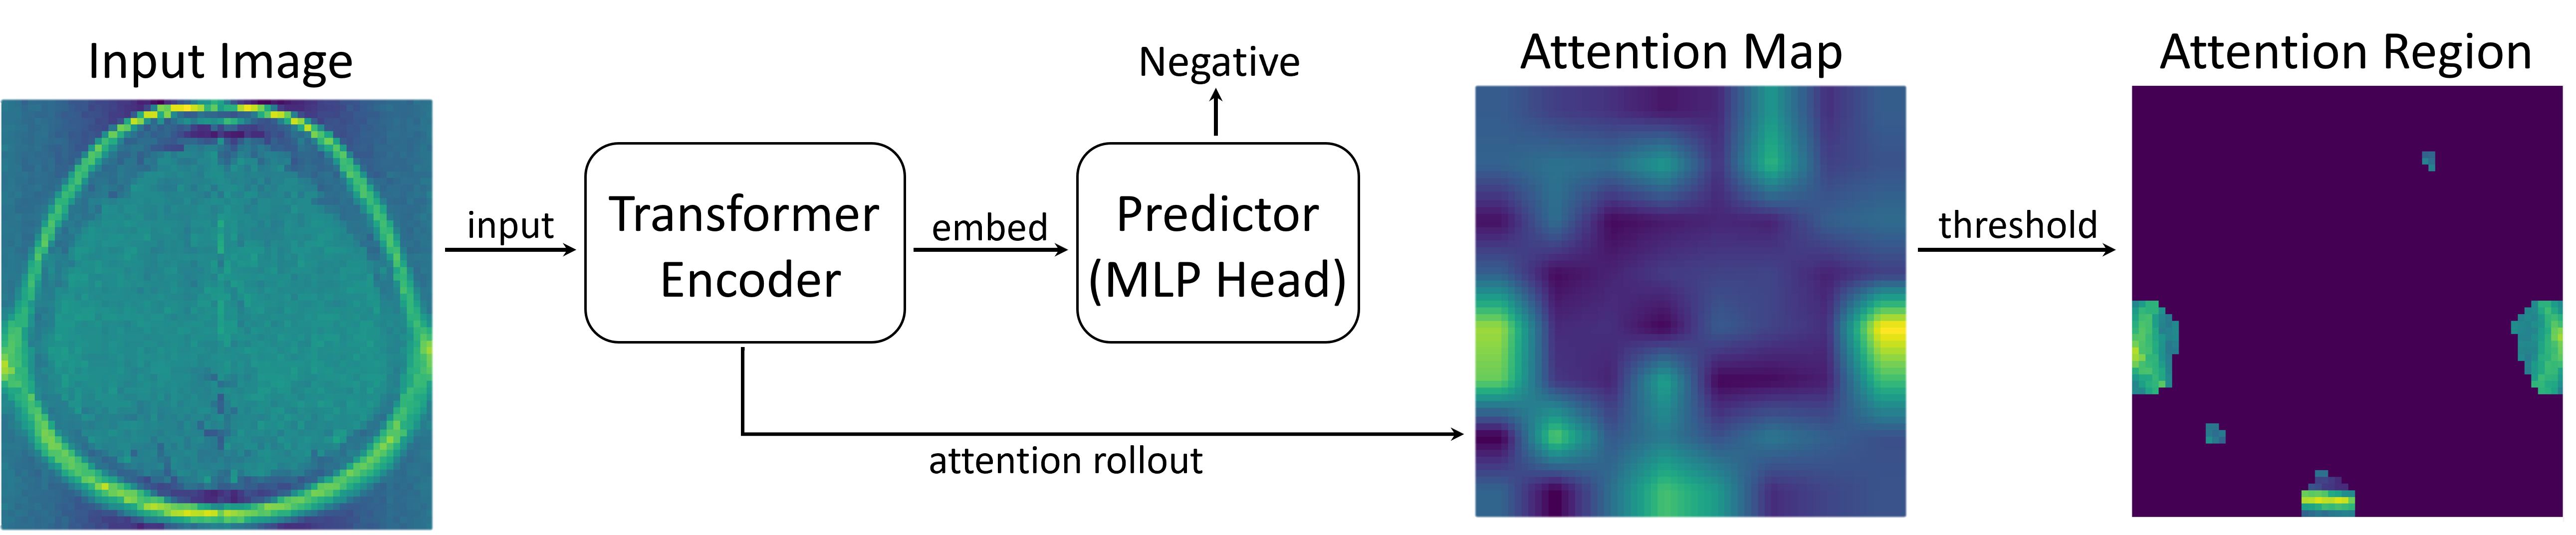

Figure 1 illustrates the problem setup considered in this study, where we applied a naive statistical test, which does not consider selection bias, and our proposed statistical test to brain image diagnosis task. The upper panel shows a brain image with a tumor region, in which we want the attentions to be declared as statistically significant (with a small -value). Here, both the naive test and the proposed test conclude that the identified attention is statistically significant with -values nearly 0. In contrast, the lower panel displays a brain image without tumor regions, in which we want the attentions to be determined as statistically not significant (with a large -value). In this case, the naive test falsely detects significance (false positive) with an almost zero -value, while the proposed method yields a -value of 0.801, concluding that it is not statistically significant (true negative).